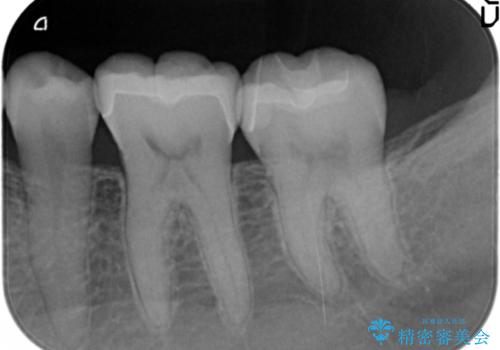

左下の奥歯2本にプラスチックの詰め物がされており、一見虫歯には見えない状態でした。

レントゲンを撮影したところ、奥歯の歯の間が虫歯が発見できました。

歯と歯の間の虫歯は、視診(見るだけ)では発見できません。

定期検診をするなら、定期的にレントゲンを撮ることをおすすめいたします。